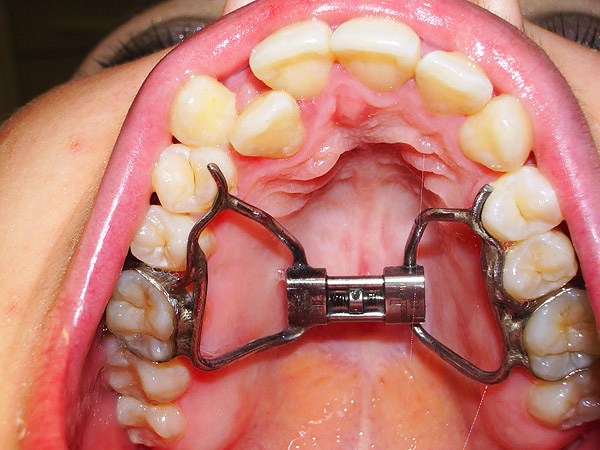

Com um estreitamento significativo da mandíbula superior, o médico pode usar estruturas de expansão, como o aparelho de Biderman, para rápida expansão palatal para tratar uma mordida cruzada (também com um parafuso, o médico define o modo de ativação). A ativação é realizada pelos pais ou pelo próprio paciente, em média uma vez a cada 7 a 10 dias.

Um exemplo de tal aparelho é mostrado na foto: